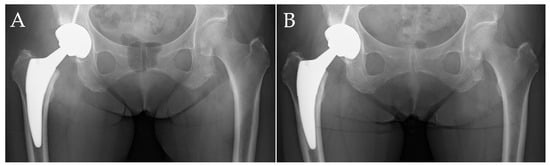

| Stress shielding (hips) | |||

| Grade 0 | 12 | 6 | 0.001 |

| Grade 1 | 10 | 28 | |

| Grade 2 | 12 | 46 | |

| Grade 3 | 2 | 11 | |

| Grade 4 | 0 | 3 | |